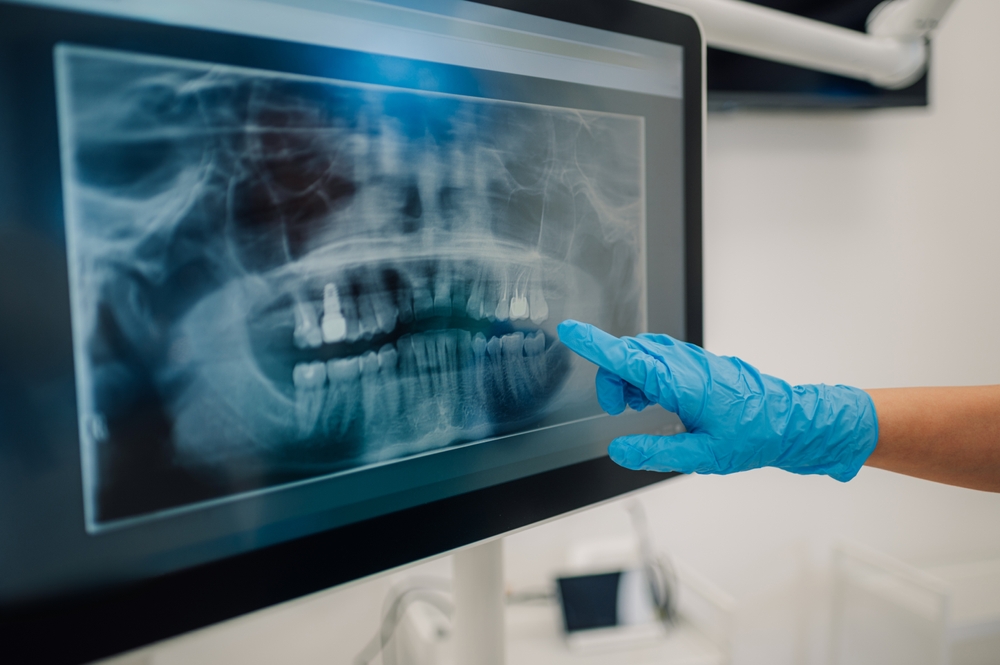

La densità ossea relativa è un dato prezioso da conoscere. Non per niente la qualità dell’osso alveolare condiziona la stabilità primaria degli impianti e determina la prognosi a lungo termine. Per ottenere misure quantitative, i clinici utilizzano di norma la tomografia computerizzata (TC), che fornisce valori in unità Hounsfield (HU). Tuttavia, la TC non sempre risulta disponibile e, in molti casi, non si giustifica a causa dei costi e della dose di radiazioni. Per risolvere questo limite, un gruppo di ricercatori russi delle principali università e centri clinici ha sviluppato un metodo rapido e a basso costo per stimare la densità ossea relativa sfruttando ortopantomografie digitali (OPT, OrtoPanTomo-grafie) analizzate con il software ImageJ.

Gli autori hanno utilizzato ImageJ 1.54i, un software gratuito e open source sviluppato dal National Institutes of Health (NIH, USA). Questo programma è ampiamente diffuso in campo medico e biologico per l’elaborazione e la misura quantitativa delle immagini digitali. Nel presente studio, i ricercatori lo hanno impiegato per calcolare il “mean gray value” (valore medio di grigio, 0–255) nelle regioni di interesse (ROI, Region of Interest).

Per garantire la riproducibilità, hanno standardizzato il flusso operativo: hanno impostato le misure iniziali, escluso le immagini con illuminazione non uniforme o con rapporto segnale/rumore (SNR, Signal-to-Noise Ratio) < 20 dB, selezionato le ROI con lo strumento poligonale e gestito più aree tramite “ROI Manager”. Infine, hanno espresso la densità in forma relativa, rapportando il valore medio della ROI d’interesse con quello di un’area di riferimento sana.